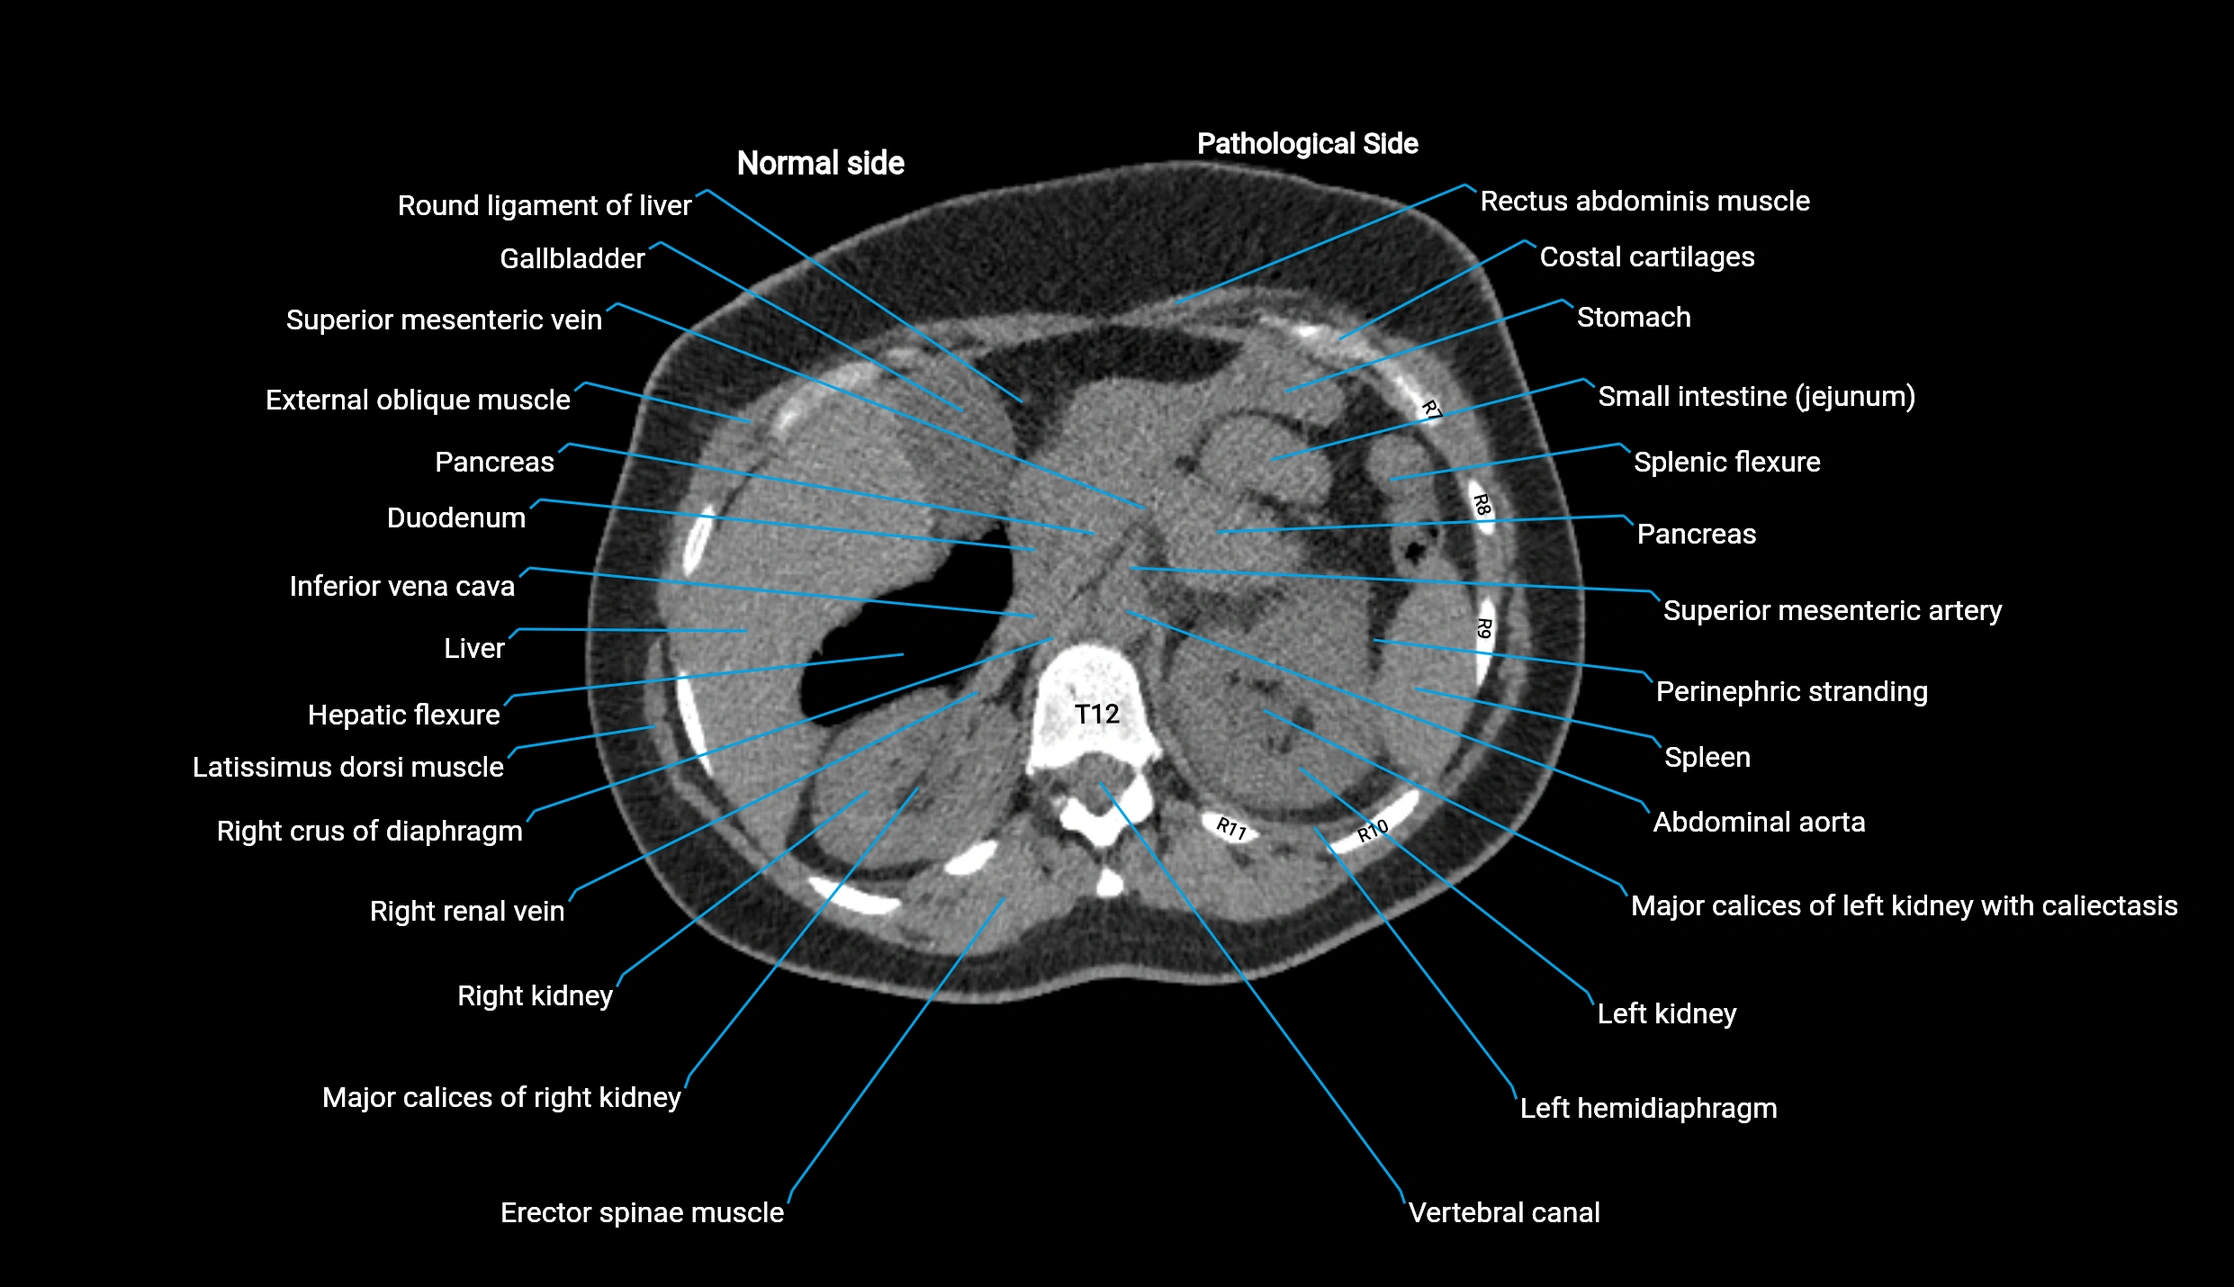

CT image

image